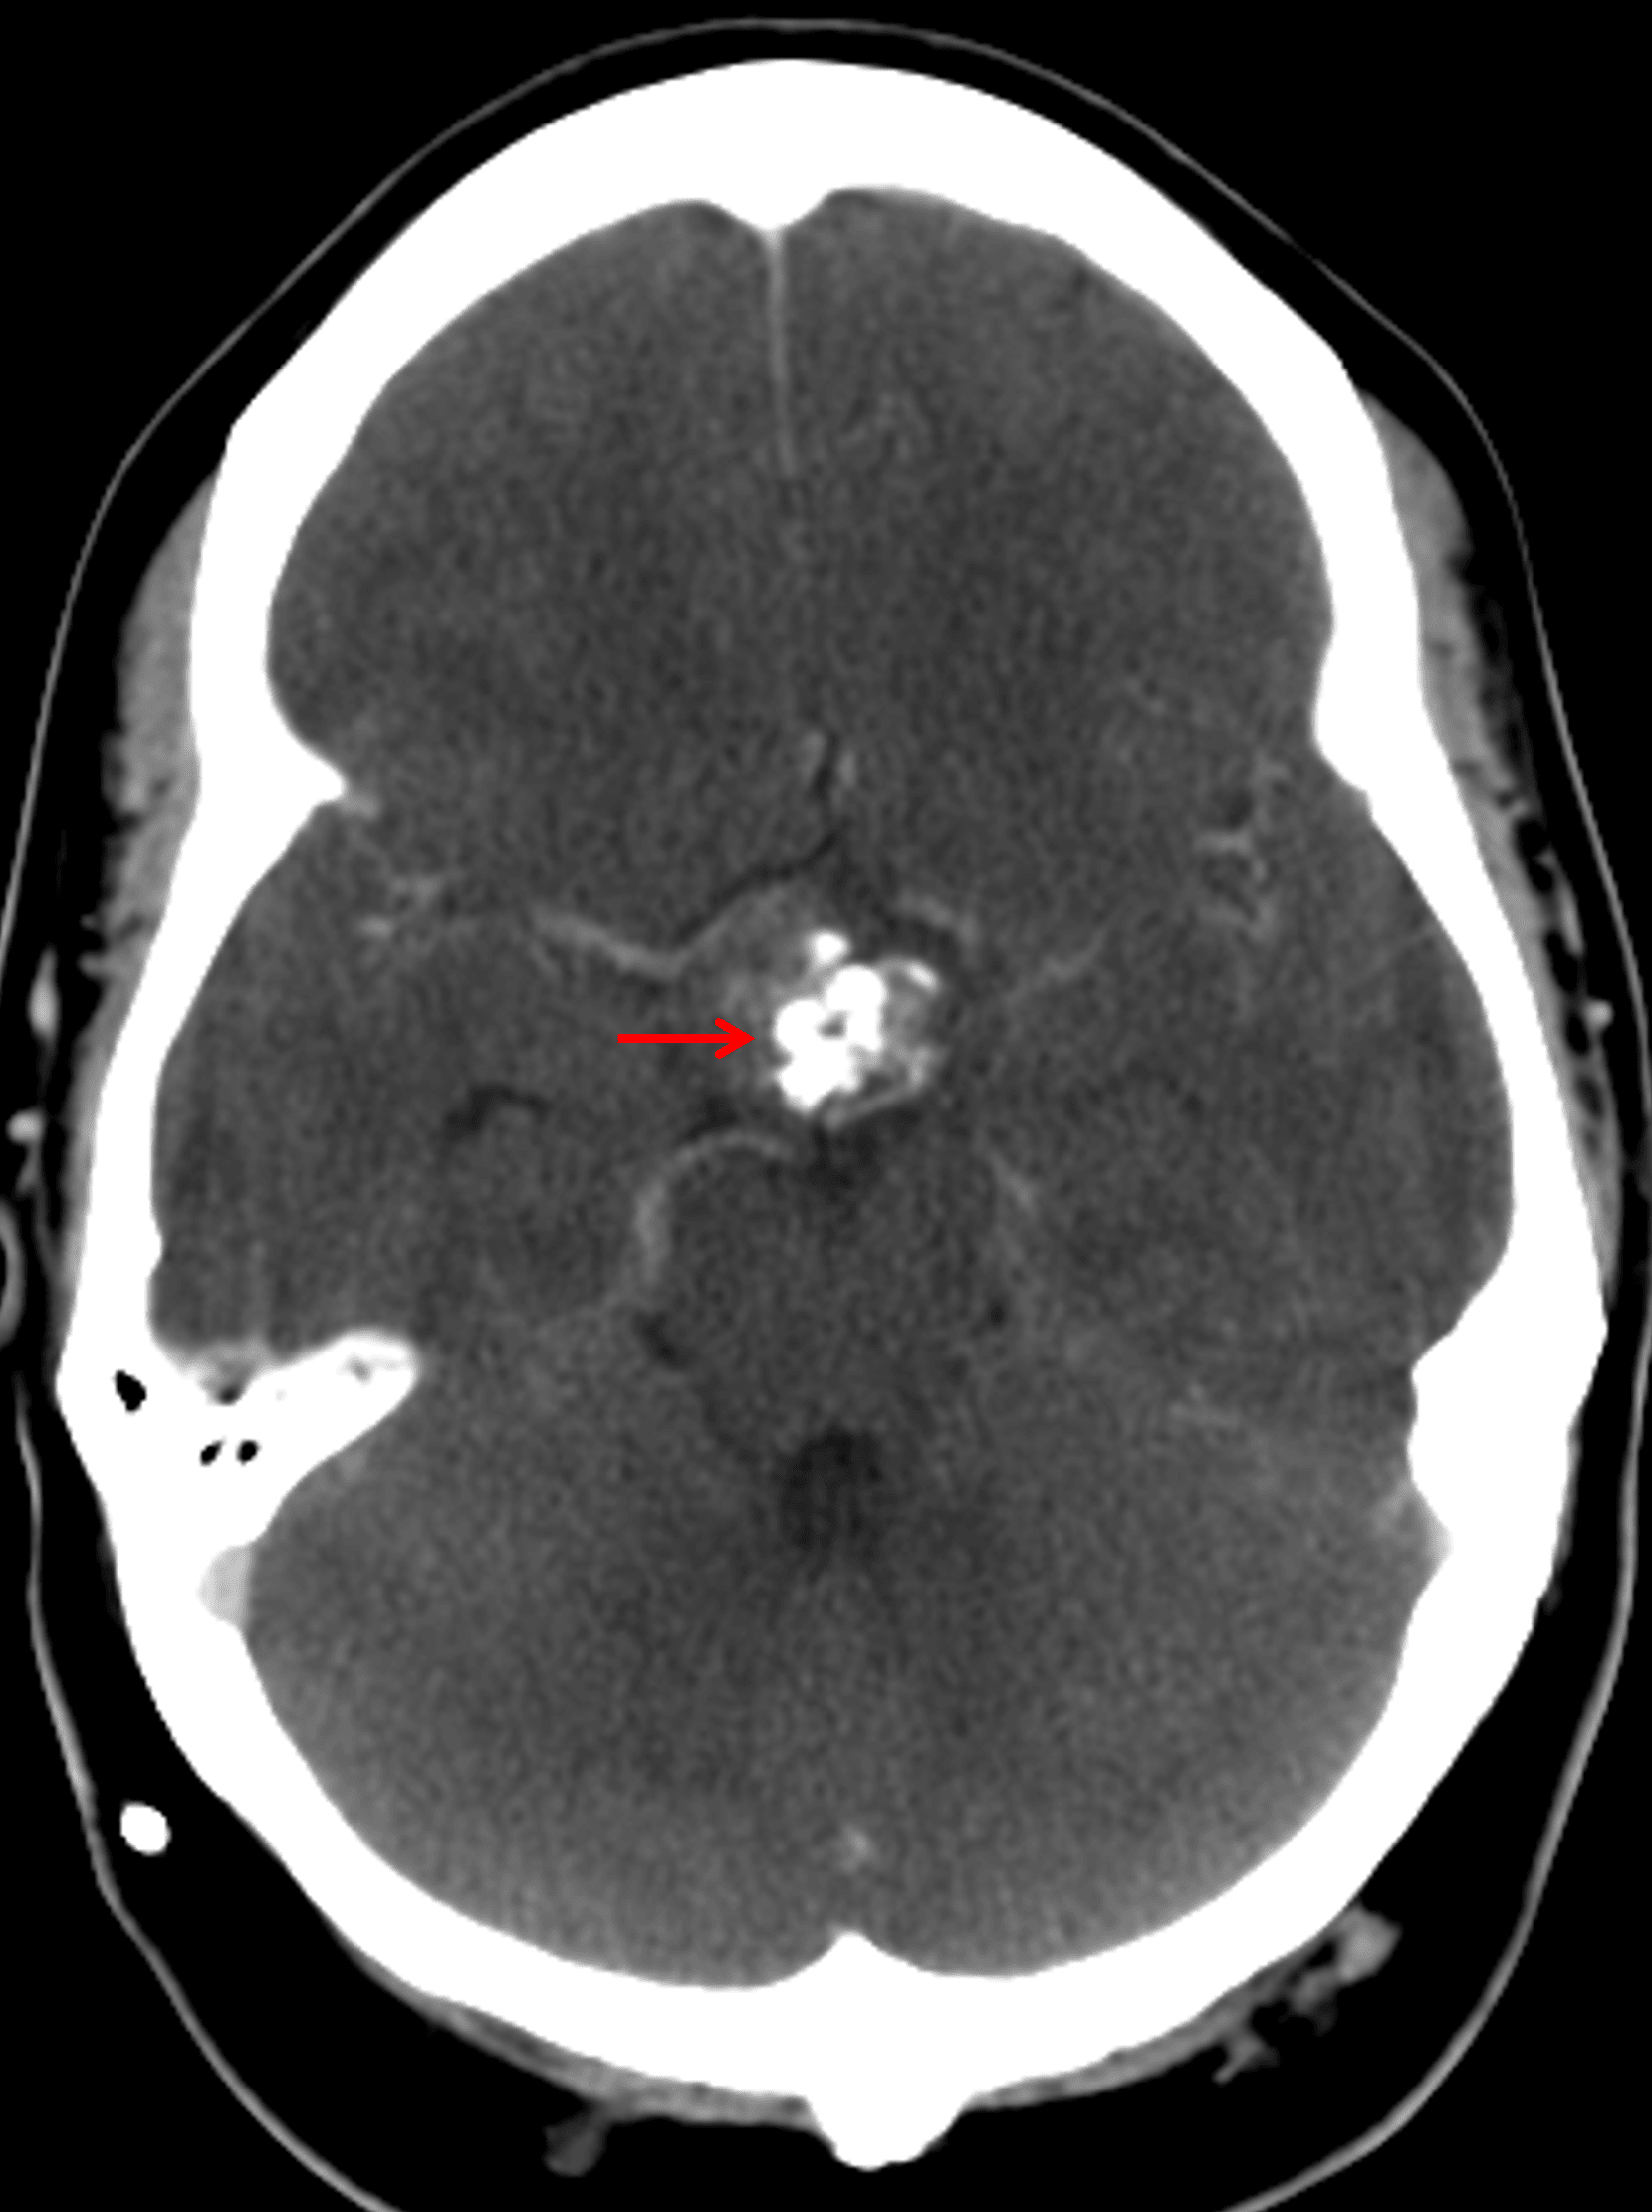

CT

- Mixed cystic and solid suprasellar mass with internal coarse calcification

- Left frontal approach ventricular shunt catheter terminating in the frontal horn of the left lateral ventricle

- Asymmetric prominence of the frontal horn of the right lateral ventricle, which may represent differential shunting

Suprasellar mass with coarse internal calcification (red arrow).